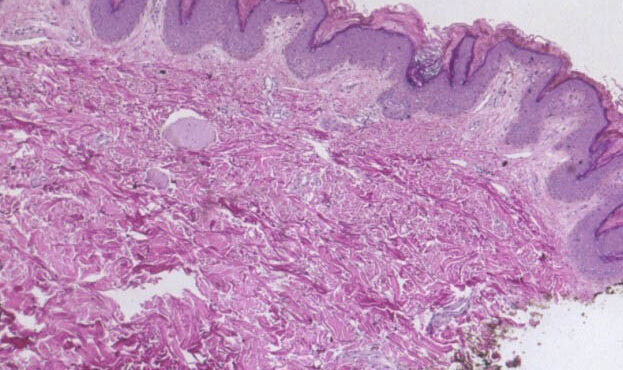

Read MorePapillary and reticular dermis = الادمة الحليمية والشبكية